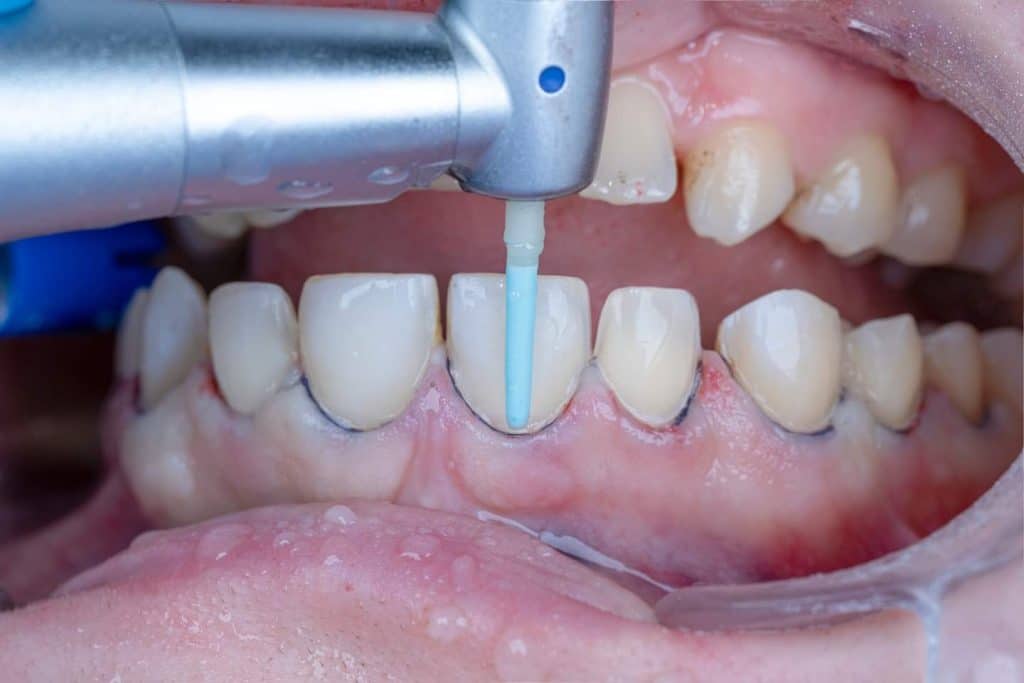

The case presented in this case report is for a 27-years-old female patient with a chief complaint of aesthetic correction for her smile. The patient was unhappy with her smile. After clinical examination, there were previous old composite veneering done poorly and incorrectly to close the multiple interdental spacing. After discussing the various treatment options (i.e., orthodontic treatment, direct, or indirect veneers), indirect ceramic veneering was selected. The step-by-step treatment protocol is presented in the images below.

Special thanks to my friend, Dr. Ali Al-Qrimli the CEO of Digital IDEA dental lab for fabrication of the ceramic veneers and the digital designing, with many thanks for the dental ceramist, Dt. Ali Kadum who did the ceramic build-up for this case.